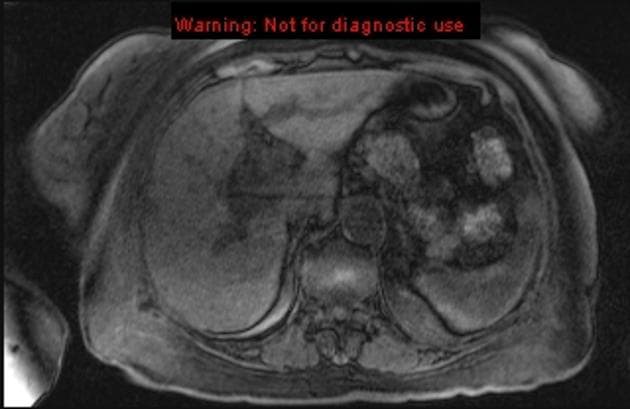

Axial T2 fat sat

U Klatskin - ung thư đường mật cửa gan

Vàng da kèm sỏi túi mật, nghi ngờ sỏi ống mật chủ. Tiền sử cắt đại tràng toàn phần do viêm loét đại tràng

- Có giãn rõ rãnh ống gan trái, với khối tổn thương nhỏ, tăng quang tối thiểu tại cửa gan (porta hepatis).

- Ống mật chủ (CBD) không giãn.

- Hình ảnh trễ với Primovist (chất cản quang hướng tế bào gan) cho thấy tăng quang tối đa ở thùy gan phải, tăng quang kém hơn ở thùy gan trái do tắc nghẽn mạn tính, và khối tổn thương tăng quang tối thiểu tại rốn gan, tổn thương này cũng biểu hiện hạn chế khuếch tán (restricted diffusion).

- MRCP cho thấy hình ảnh hẹp điển hình tại vị trí nối giữa ống gan phải và ống gan trái, lan vào ống gan chung (gây tắc nghẽn đáng kể nhất đối với ống gan trái).

U Klatskin - ung thư đường mật cửa gan (Klatskin tumor - hilar cholangiocarcinoma)

- "Ung thư đường mật cửa gan (u Klatskin) thường khởi phát bằng vàng da không đau và giãn ống mật khu trú ở thùy gan bị ảnh hưởng, thường không kèm giãn ống mật chủ xa."

- "Chụp hình pha muộn với chất cản quang hướng gan như Primovist giúp phân biệt khối u (tăng quang tối thiểu, hạn chế khuếch tán) với các đoạn hẹp lành tính và đánh giá mức độ tổn thương chức năng nhu mô gan."

- "Dấu hiệu hình ảnh điển hình là khối xâm lấn tại cửa gan gây hẹp đường mật trung tâm, thường gặp nhất tại nơi hợp lưu của ống gan phải và trái."